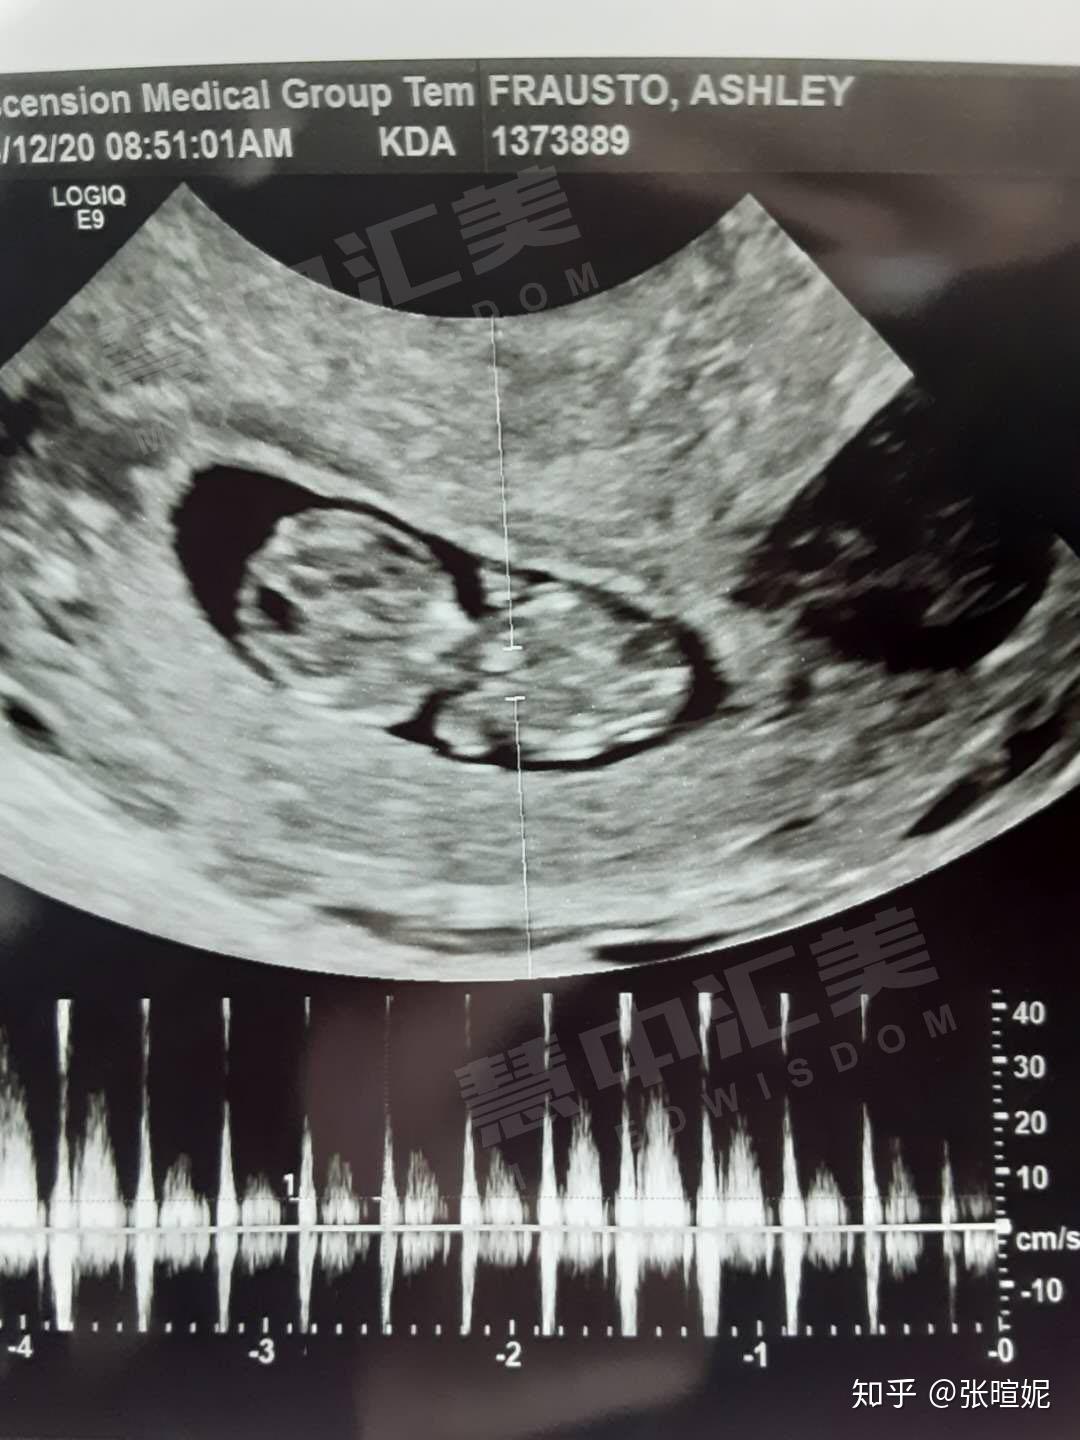

剩下的4顆優質受精卵我就是通過胚胎冷凍技術存放在了我管理的醫院,到今年1月份又解凍了1顆凍胚,現在聽到了胎心,已經三個多月了,醫生說二寶特別健康。